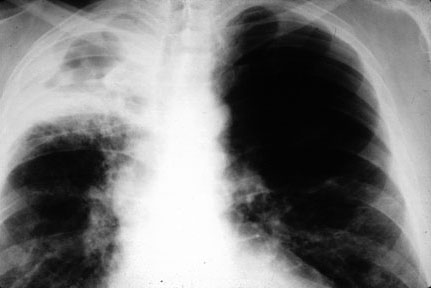

- Secondary pulmonary TB (reactivation) is characterized by a

focus of infection and granuloma formation usually in the apex

of the lung. The small granulomas (tubercles) eventually coalesce to form larger areas

of consolidation with central caseating necrosis. Regional lymph nodes contain caseating

granulomas.

- Progressive pulmonary TB: Primary or secondary TB may go on to

heal as caseating granulomas are replaced by fibrosis

and calcification. However, cases do not heal spontaneously or with therapy and progress

to form cavities or spread to other parts of the lung and other organs of the body through

lymphatic channels and the blood stream. This type of spread is known as miliary tuberculosis.